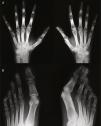

Radiografía de manos (A) en la que se observa reacción perióstica en radio. Ensanchamiento distal con cambios hipertróficos en los penachos y áreas de osteolisis en los mismos, de las que es un buen ejemplo el cuarto dedo de la mano derecha. Desmineralización yuxtaarticular. Radiografía de pies (B) en la que se observan marcados cambios destructivos en falanges distales, algunas con morfología aplanada y penachos distales hipertróficos con proliferación ósea. Marcada deformidad de los dedos en palillo de tambor.

Presentación clínicaVarón de 30 años de edad, diagnosticado de hipertensión arterial pulmonar primaria sin cortocircuito asociado a los 2 años de edad, en seguimiento por Cardiología Pediátrica desde entonces. No tenía otros antecedentes médicos personales ni familiares de interés, incluyendo enfermedades reumáticas y psoriasis. A los 29 años comenzó a presentar episodios de poliartritis simétrica y aditiva que afectaban rodillas, tobillos, hombros, carpos y metacarpofalángicas, con importante limitación funcional. En la exploración física destacaba además la presencia de cianosis generalizada y acropaquias, sin lesiones cutáneas ni ungueales sugestivas de psoriasis. En la analítica se evidenció reactantes de fase aguda normales, factor reumatoide negativo y anticuerpos anti-CCP positivos a título bajo en una determinación aislada. El estudio radiográfico mostró acro-osteolisis en falanges distales de manos y pies, más severa en esta última localización, en la que algunas falanges adoptaban una morfología piramidal o con el extremo aplanado, y en ambas localizaciones existía importante neoformación ósea, más marcada en manos (figs. 1 y 2). En ambos carpos se observaba además pinzamiento radiocarpiano y de articulaciones intercarpianas, mayor en el izquierdo, sin erosiones. En huesos largos (tibias, peronés y radios) se evidenciaban corticales de aspecto algodonoso y despegamiento perióstico compatibles con periostitis. La gammagrafía ósea mostraba moderada hipercaptación en falanges distales de ambas manos, así como carpo y radio derechos y zona teórica de semilunar izquierdo.